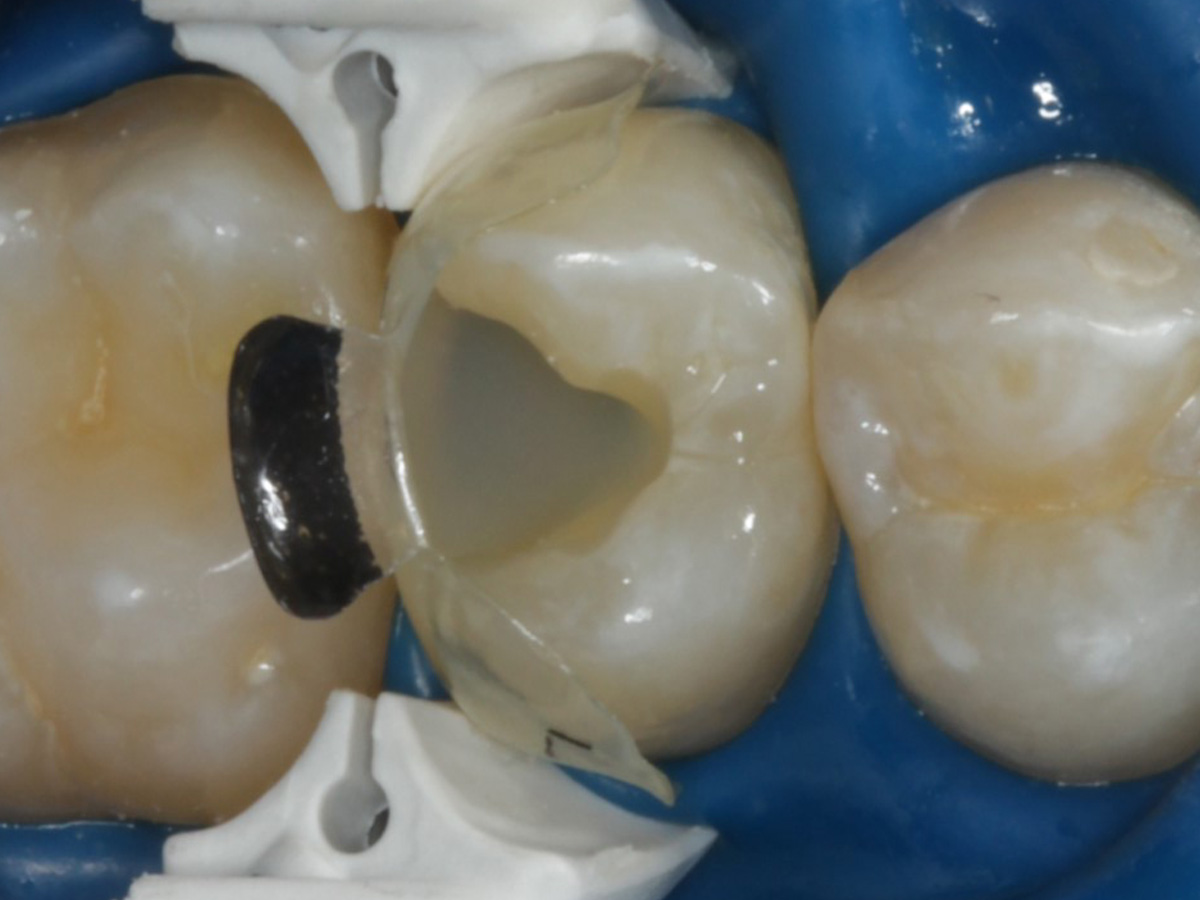

Abbildung 10

Nach Spray und Trocknung der Kavität: perfekte Adaptation der Matrize insbesondere tief subgingival

Abbildung 16

Nach Anbringung des Bioclear Twin Ring Universal und Lichthärtung des Einkomponentenadhäsivs